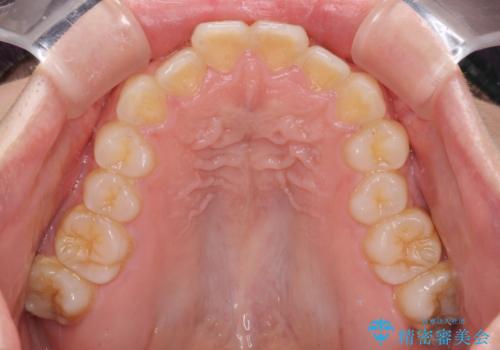

- 前歯が突出しているために口が閉じられないとのことで来院された患者様です。

上下ともに顎が小さく、歯列が前方に突き出していたため、上下左右の第一小臼歯4本を抜歯し、口元の突出感を改善していくこととしました。